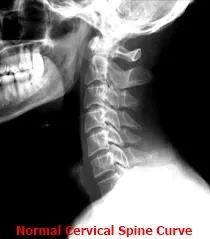

C_spine___normal.jpg This loss of normal (C-shaped forward) C_spine___kyphotic.jpg cervical curvature  is the result of the cervical acceleration/deceleration syndrome, and can be responsible for many positive orthopedic and neurological examination findings contributing to the patient’s symptomatology. X-rays cannot demonstrate microscopic tears nor show inflammation in the soft tissue (ligaments, tendons, muscle, cartilage, etc) which is one of the leading causes of the pain and soreness that one experiences following motor vehicular accident trauma. X-rays are the most cost effective study to rule out ligament insufficiency, bone pathology and vertebral misalignment leading to abnormal musculoskeletal mechanics.

• Recent epidemiological studies have shown that most injury rear impact accidents occur at crash speeds of 6 mph to 12 mph--the majority at speeds below the threshold for property damage to the vehicle. A number of risk factors in rear impact accident injury have now been verified including: rear (vs. other vector) impact, loss of cervical lordotic (C-shaped forward) curve, pre-existing degenerative changes, the use of seat belts and shoulder harness, poor head restraint geometry, non-awareness of the impending collision, female gender, and head rotation at impact.